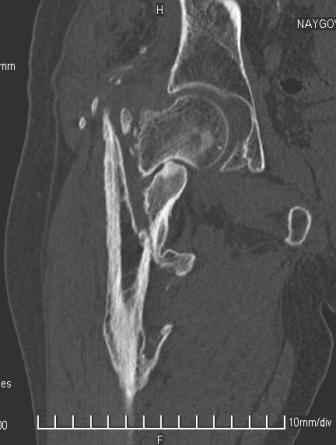

Сросшийся со смещением чрез-подвертельный перелом

Больной Н. 44 года травма 1,5 года назад июнь 2008 года чрез-под вертельный перелом правого бедра. Во время лечения у больного развился алк. делирий, проводилось консервативное лечение перелома.

Беспокоят боли, укорочение конечности. Укорочение 3 см. Ногу поднимает, сгибание ограничено, ротационные движения в полном объеме. На КТ перелом сросся за счет костной мозоли. Что делать?

Протез? Если «да» Можно ли обойтись стандартной ножкой Corail?

Или межвертельная остеотомия?